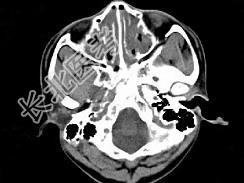

- 单项选择题男,14岁, 持续性鼻塞、嗅觉减退,流脓涕数年, CT检查如图,最可能的诊断为 ( )

A、鼻炎及鼻窦炎

B、鼻及鼻窦息肉

C、过敏性鼻炎及鼻窦炎

D、恶性肉芽肿

E、上颌窦癌